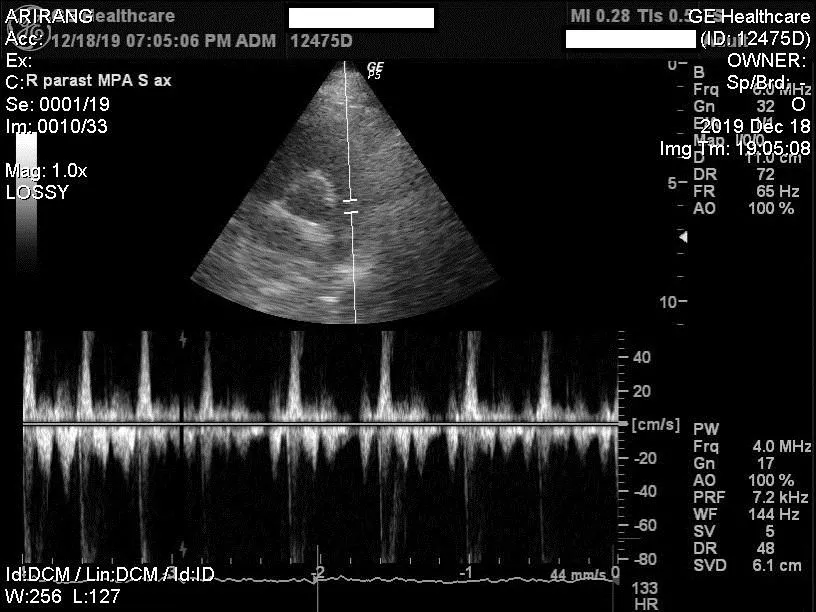

Using something called 'Doppler' we can also assess the pattern of blood flow and the speed of blood flow throug the various valves in the heart.

Echocardiography is a very important tool in diagnosing conditions like cardiomyopathy (heart muscle disease), chronic valvular disease or pericardial effusion (heart sac filling up with liquid).